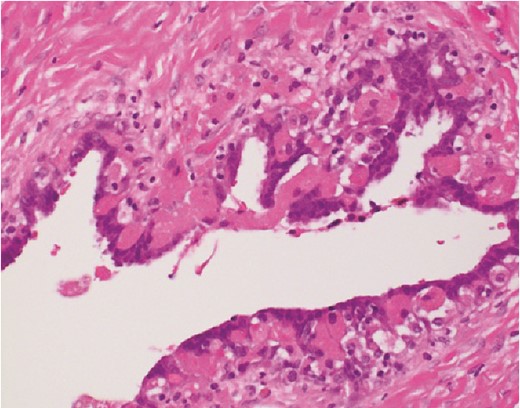

The histological findings with hematoxylin-eosin stain (H&E) revealed a cystic lesion with a very small and relatively dense stroma under the epithelium in the left paratubal region (Fig. 3). This stroma is CD10 positive in a small portion, suggesting the possibility of endometriosis (Fig. 4). Moreover, adenocarcinoma is arises from this cyst (Figs 5 and 6). There was no disseminated lesion in bilateral adnexa and uterus.

With these histological findings, we diagnosed the tumor as an endometrioid carcinoma arising from the paraovarian cyst.